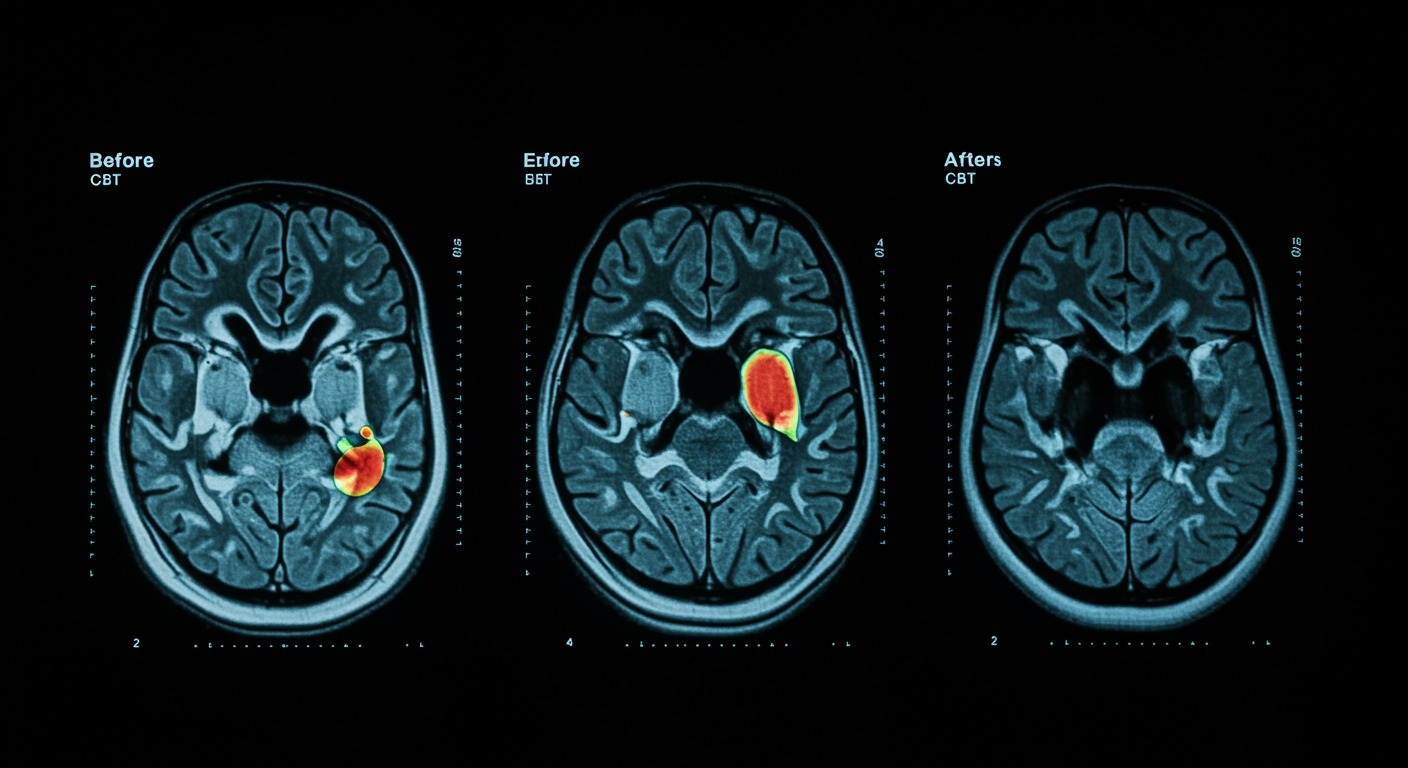

How does CBT change the depressed brain?

Yes. Cognitive behavioral therapy measurably changes brain activity in limbic, striatal, cingulate, and frontal areas, partially normalizing neural patterns associated with depression and reducing negative cognitive biases. A systematic review of 14 task-based fMRI studies published in the Journal of Affective Disorders shows that CBT produces objective, measurable neurobiological changes that correlate with symptom improvement.

This systematic review provides the neurobiological proof that CBT isn’t just “talk therapy” - it’s literally rewiring the brain. The fact that we can see measurable changes in limbic, striatal, cingulate, and frontal areas on fMRI scans is remarkable. These are exactly the brain regions we know are dysfunctional in depression. The limbic system processes emotions, the striatum is involved in motivation and reward, the cingulate cortex handles attention and emotion regulation, and the frontal areas manage executive function and decision-making. CBT is essentially teaching the brain new ways to process information and emotions, and we can now see this happening in real-time through brain imaging.

This systematic review analyzed longitudinal fMRI studies examining brain activity changes in depressive patients undergoing cognitive behavioral therapy. The researchers focused on task-based fMRI studies that measured brain function before and after CBT treatment, allowing them to identify specific neural changes associated with therapeutic improvement. The review examined changes across multiple brain regions and their relationship to symptom remission.

The review revealed that CBT produces a consistent pattern of brain changes: reduced limbic reactivity (particularly in amygdala and hippocampus), increased striatal reward responsiveness, and altered activity in cingulate and prefrontal regions. These changes were most consistently associated with symptom improvement in the subgenual anterior cingulate cortex, where multiple studies found significant correlations between neural activity changes and clinical recovery. The findings suggest that CBT works by normalizing the neural patterns underlying negative cognitive biases, with measurable brain changes that correlate with therapeutic success.